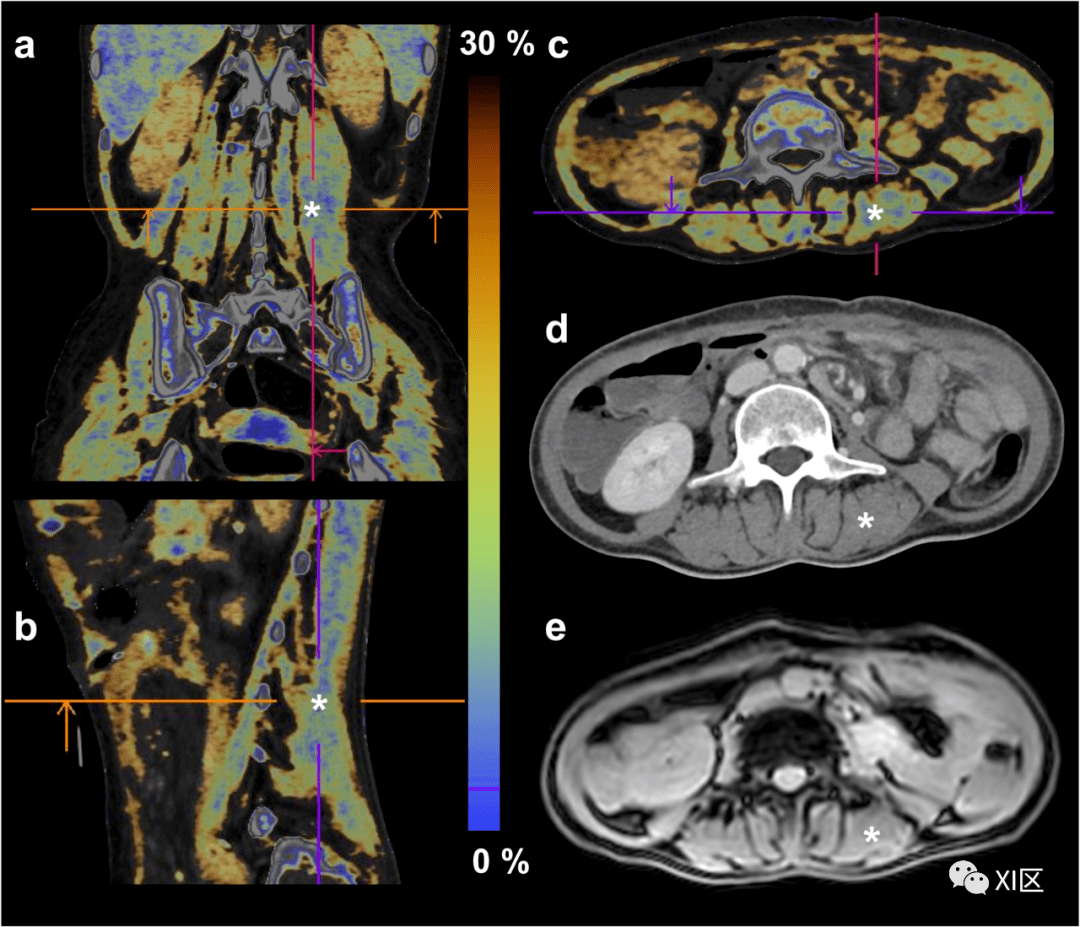

双能ct骨骼肌脂肪定量